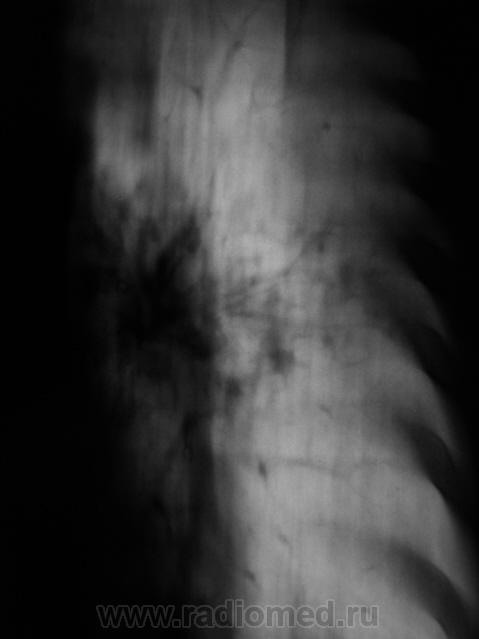

1 срез в боковой проекции.

Приложения:

Следующий срез.

Доделали один срез - 5 см. в прямой проекции.